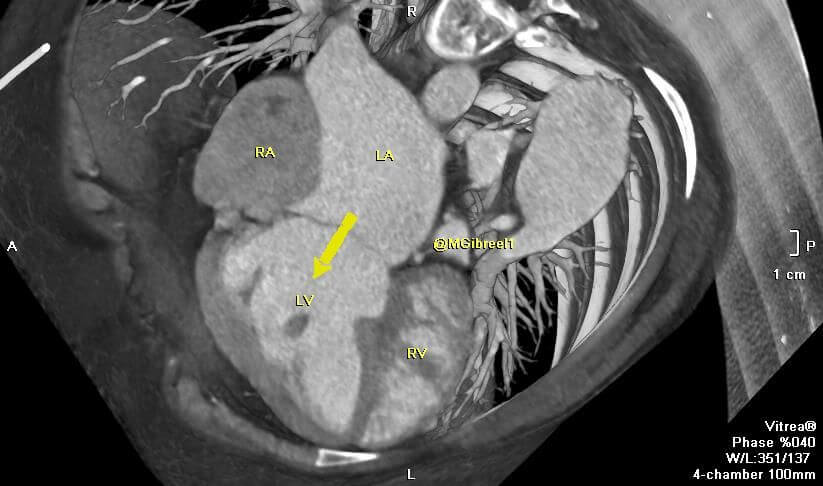

Criss-cross heart

Mohamed Gibreel , FEBR (Fellowship of Egyptian Board of Radiology ) Cardiac imaging consultant at Aswan heart center -Magdi Yacoub Foundation , Egypt